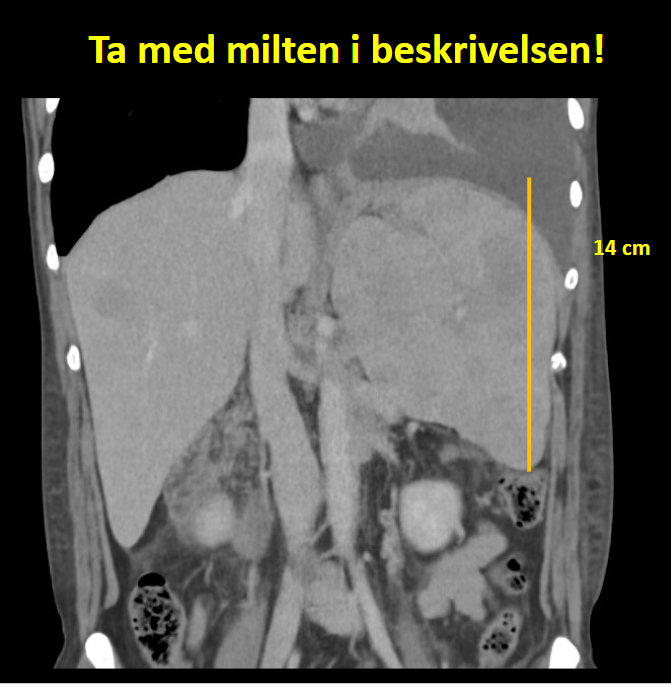

Lymfom/ Lugano ble godt oppsummert av Audun Berstad, også han fra DnR: Velg inntil 6 targetlesjoner, mål i 2 perpendikulære plan. Målbare: Lkn. > 15 mm lengde, ekstranodale over 10 mm. Ved konglomerater: mål “separate” lymfeknuter. Ta med milten i beskrivelsen, mål craniocaudal/ vertikal diameter på koronale reformat . Angi hvor det er egnet for biopsi.